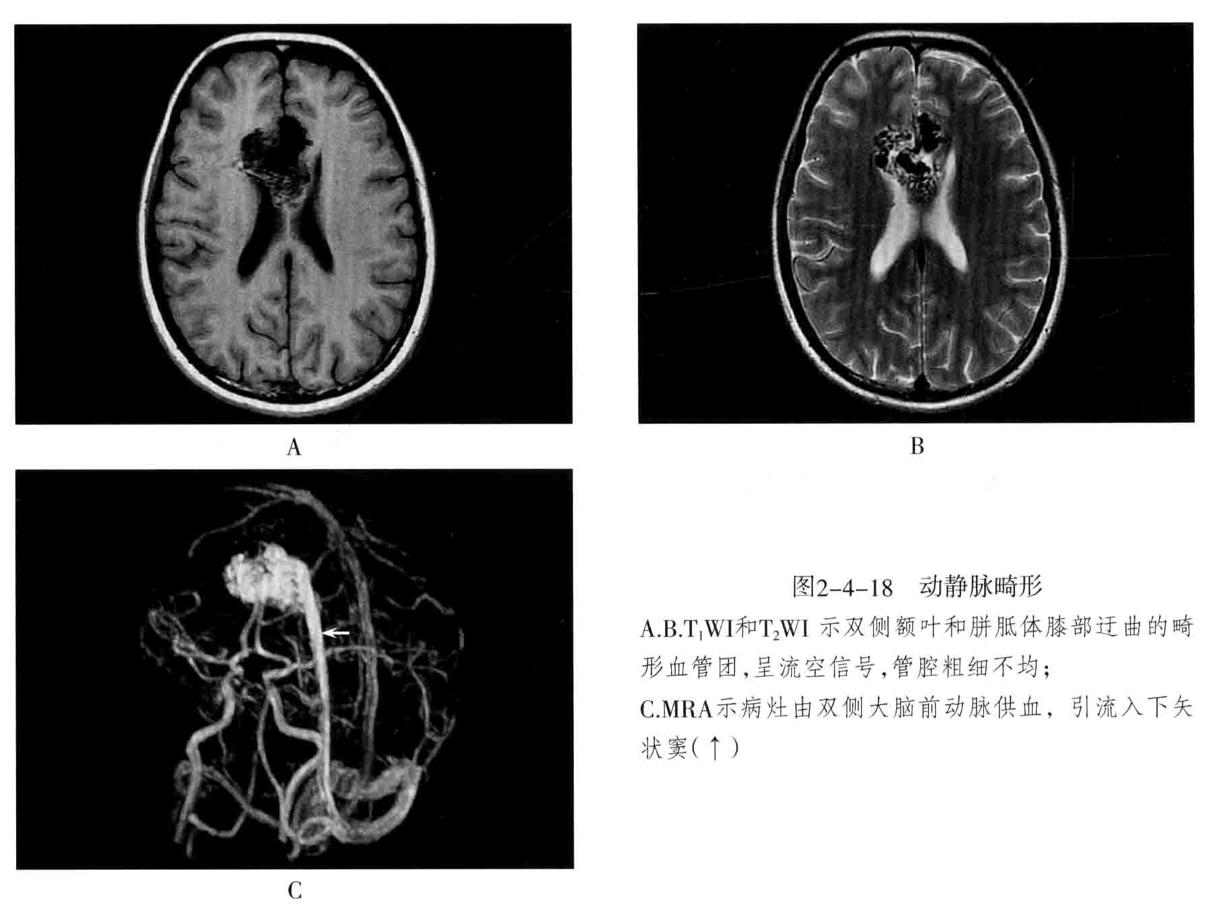

• 动静脉畸形(AVM ): 迂曲扩张的 供血动 脉与 引流静脉 之间无正常毛细血管,而是通过 畸形的血管 直接相通,形成 异常的血管团 。畸形血管易破裂出血,由于动静脉短路,周围脑组织因缺血而发生萎缩,称为“盗血”现象。多见于大脑中动脉分布的脑皮质,也可发生于侧脑室脉络丛、硬脑膜、软脑膜、小脑及脑干。主要临表:出血(蛛网膜下腔出血及脑实质出血)、癫痫、头痛。

3. MRI检查:畸形血管团由于流空效应,在T1WI及T2WI上均无信号,供血动脉表现为低或无信号。不伴有出血时,病灶无占位效应及周围水肿,邻近脑组织呈萎缩。

4. 鉴别诊断: 海绵状血管瘤在T1WI、T2WI上均混杂信号,境界清楚病灶内无流空效应,T2WI病灶周围可见低信号含铁血黄素环,使病灶呈“爆米花”状,具有特征性,增强扫描病灶轻度-明显强化(与病灶内血栓及钙化量多少有关,血栓少则强化明细)。